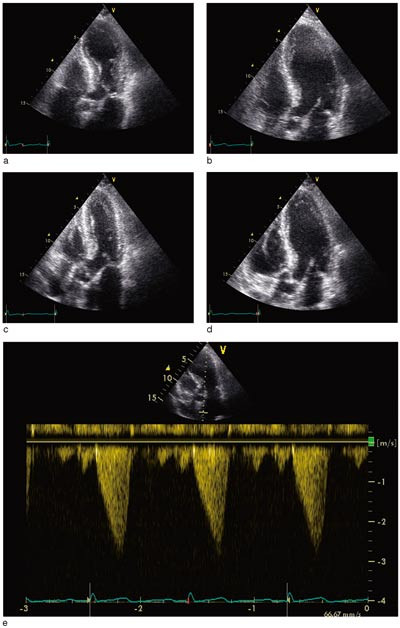

Pasient 2. 53 år gammel kvinne, som de siste to måneder før det aktuelle hadde vært plaget med erosiv, seropositiv revmatoid artritt i venstre hånd. Ellers hadde hun stort sett vært frisk. I forbindelse med en ferietur ble hun innlagt i sykehus i Polen grunnet sentrale brystsmerter og dyspné. Ved klinisk undersøkelse var det ingen vesentlige patologiske funn, bortsett fra lette sibili over lungene. Arterielt blodtrykk var 135/80 mm Hg, pulsfrekvens 80 per minutt. Klinisk og røntgenologisk var det mistanke om pneumoni, og hun fikk behandling med penicillin. EKG viste tydelig inversjon av T-takken i avledningene I. II, III, AVL og AVF samt V₃ – V₆. Ekkokardiografi viste akinesi av apeks og apikale segmenter av venstre ventrikkel. Det ble fire dager etter innleggelse utført koronar angiografi med ventrikulografi av venstre ventrikkel (fig 1). Man fant helt normale koronararterier. Venstre ventrikkel viste imidlertid akinesi i apikale segment og apikale deler av nedre og fremre vegg, det samme som ved ekkokardiografi. Laboratorieprøvene viste en stigning av troponin I til maksimalt 0,15 ng/100 ml (fra 0,03 ng/100 ml), for øvrig var det upåfallende blodprøveresultater.

Pasient 3. 76 år gammel kvinne, som gjennom mange år hadde fått substitusjonsbehandling for hypotyreose. Ellers hadde hun stort sett vært frisk. Etter å ha deltatt i seniordans følte hun seg sliten og fikk ikke sove på grunn av smerter i venstre skulder. Morgenen etter hadde hun fortsatt smerter i skulderen og også i venstre side av thorax. Vel et halvt døgn etter smertedebut ble hun innlagt i sykehus. Hun var ved innleggelsen smertefri, og det var ingen kardiopulmonale svikttegn. Arterielt blodtrykk var 120/85 mm Hg, pulsfrekvensen 64 per minutt. Temperaturen ble målt til 38,1 °C. Ved auskultasjon fant man en systolisk bilyd grad III over prekordiet, ellers var det ingen vesentlige funn ved organstatus. EKG ved innkomst viste sinusrytme og lett ST-elevasjon i avledningene I, II og V₂ – V₆. Dagen etter innkomst var det noe mer tydelig ST-elevasjon i II, III og AVF, men i V₂ – V6 så man dype, negative og symmetriske T-takker uten ST-elevasjon. Det tilkom ingen Q-takker. Senere var det fullstendig normalisering av EKG (fig 2). Ekkokardiografi innkomstdagen viste akinesi av apex cordis og apikale tredel av venstre ventrikkel (fig 3a, 3b). Det var tydelig systolisk anterior bevegelse («SAM») av fremre mitralklaff, med betydelig trykkgradient i venstre ventrikkels utløpstrakt, målt til 45 mm Hg med doppler (fig 3e). Det var lettgradig mitralklaffinsuffisiens. Kontrollundersøkelse neste dag viste ingen vesentlig endring, men kontrollekkokardiografi fem dager etter innkomst viste tilnærmet full normalisering av venstre ventrikkels kontraktilitet (fig 3c, 3d). Trykkgradienten i venstre ventrikkels utløpstrakt var redusert til 20 mm Hg.

I rapporter fra Japan er det beskrevet et klinisk syndrom som imiterer akutt hjerteinfarkt, men som ved nærmere undersøkelser viser transitorisk apikal ballonering av venstre ventrikkel, uten koronarstenoser av betydning (1, 2). Først nylig er det kommet rapporter om tilstanden også utenfor Japan (3, 5). Foruten reversibel patologisk veggbevegelse av apikale segmenter av venstre ventrikkel (fig 1) består dette syndromet av forbigående EKG-forandringer (fig 2) og torakale symptomer. Det foreligger ingen epikardiale koronarstenoser av betydning eller vasospasme, og det er beskjeden stigning i hjerteinfarktmarkører. Ofte utløses tilstanden av emosjonelt eller fysisk stress, men også kirurgiske inngrep, traumer og infeksjoner kan være utløsende årsaker (3, 6, 7).

Hos mange av pasientene med transitorisk apikal ballonering av venstre ventrikkel er det observert obstruksjon i ventrikkelens utløpstrakt (2, 13), noe vi også observerte hos en av våre pasienter (fig 3). Det antas at noen pasienter ut fra hjertets anatomi og geometri er predisponert for obstruksjon i venstre ventrikkel, og at dette manifesteres ved kraftig adrenerg stimulasjon (13). Et prominerende basalt interventrikulærseptum, sammen med redusert venstre ventrikkel-volum, kan være årsaken til at kvinner er predisponert for obstruksjon i venstre ventrikkels utløpstrakt. Obstruksjon med trykkgradient i ventrikkelens utløpstrakt kan gi betydelig trykkøkning i apikale del av ventrikkelen, og dette kan være en del av forklaringen på hvorfor alltid apikale segmenter av venstre ventrikkel er akinetiske ved dette syndromet (7). Det finnes imidlertid flere andre forklaringer, blant annet at venstre ventrikkels apeks ikke har trelags myokardstruktur, og at apeks er grensesonen mellom perfusjonsområdene til de store koronararteriene (2).